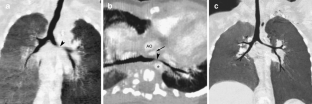

Fig. 2